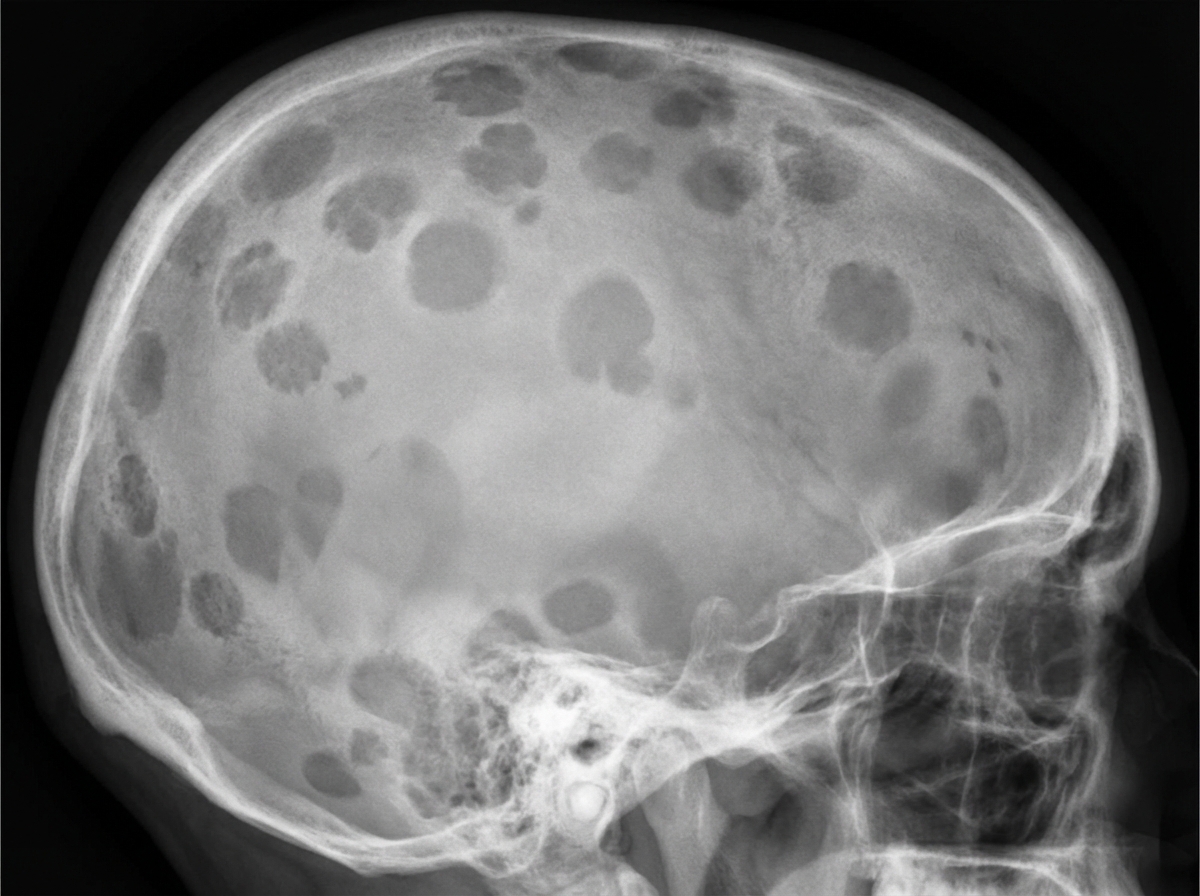

A 70-year-old man comes to the physician because of progressive fatigue and lower back pain for the past 4 months. The back pain worsened significantly after he had a minor fall while doing yard work the previous day. For the past year, he has had a feeling of incomplete emptying of his bladder after voiding. His vital signs are within normal limits. Examination shows bilateral paravertebral muscle spasm, severe tenderness over the second lumbar vertebra, and mild tenderness over the lower thoracic vertebrae. Neurologic examination shows no abnormalities. His hemoglobin is 10.5 g/dl, alkaline phosphatase is 110 U/L, and serum calcium is 11.1 mg/dl. An x-ray of the skull is shown. Which of the following is the most appropriate next step in diagnosis?